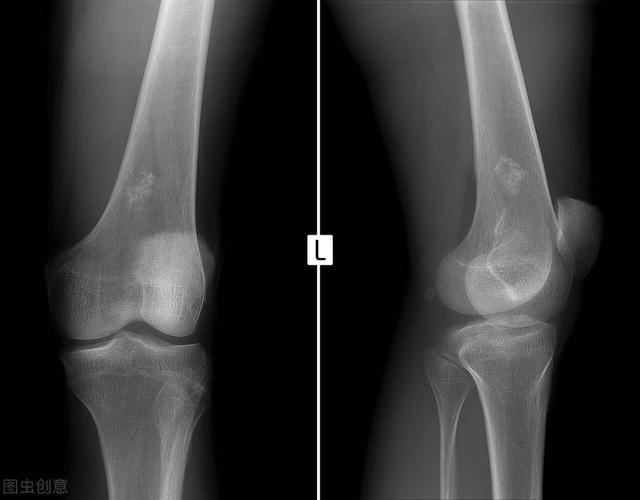

科学网 膝关节骨关节炎拍了x片还要做磁共振检查么 什么是膝骨关节炎磁共振mri检查的recht分级标准 高绪仁的博文

科普 退行性骨关节炎的分期诊疗 新闻频道 手机搜狐